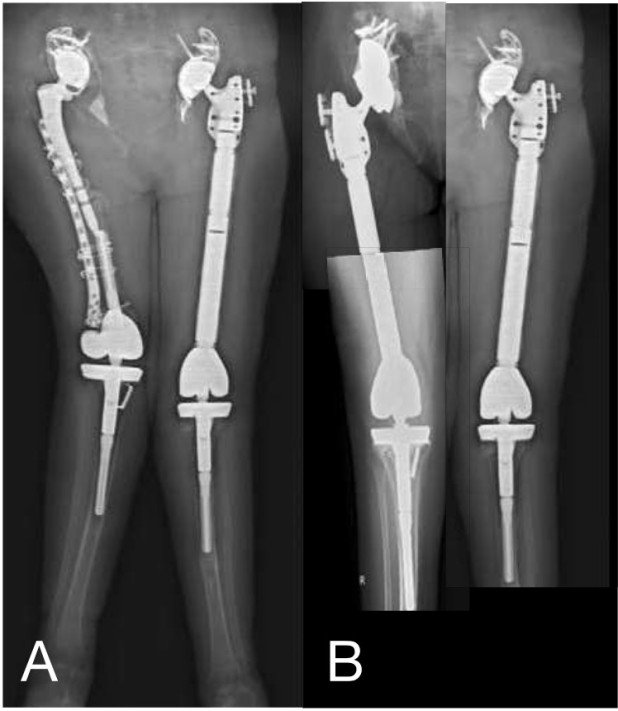

Fall 4

51-jährige Patientin hatte aufgrund einer Rheumatoiden Arthritis bereits mehrere Operationen an beiden Hüften und Knien hinter sich (Abb.7). Auf der linken Seite wurde ein Ersatz des Totalen Femur (Oberschenkelknochen) mit Hüft- und Kniegelenk durchgeführt. Die Knochenqualität im rechten Oberschenkel war so schlecht, dass nach Lockerung der Pfanne und bei ungenügender Prothesenverankerung und Instabilität im Oberschenkelschaft auch ein Totaler Femurersatz mit komplexer Beckenrekonstruktion durchgeführt werden musste.